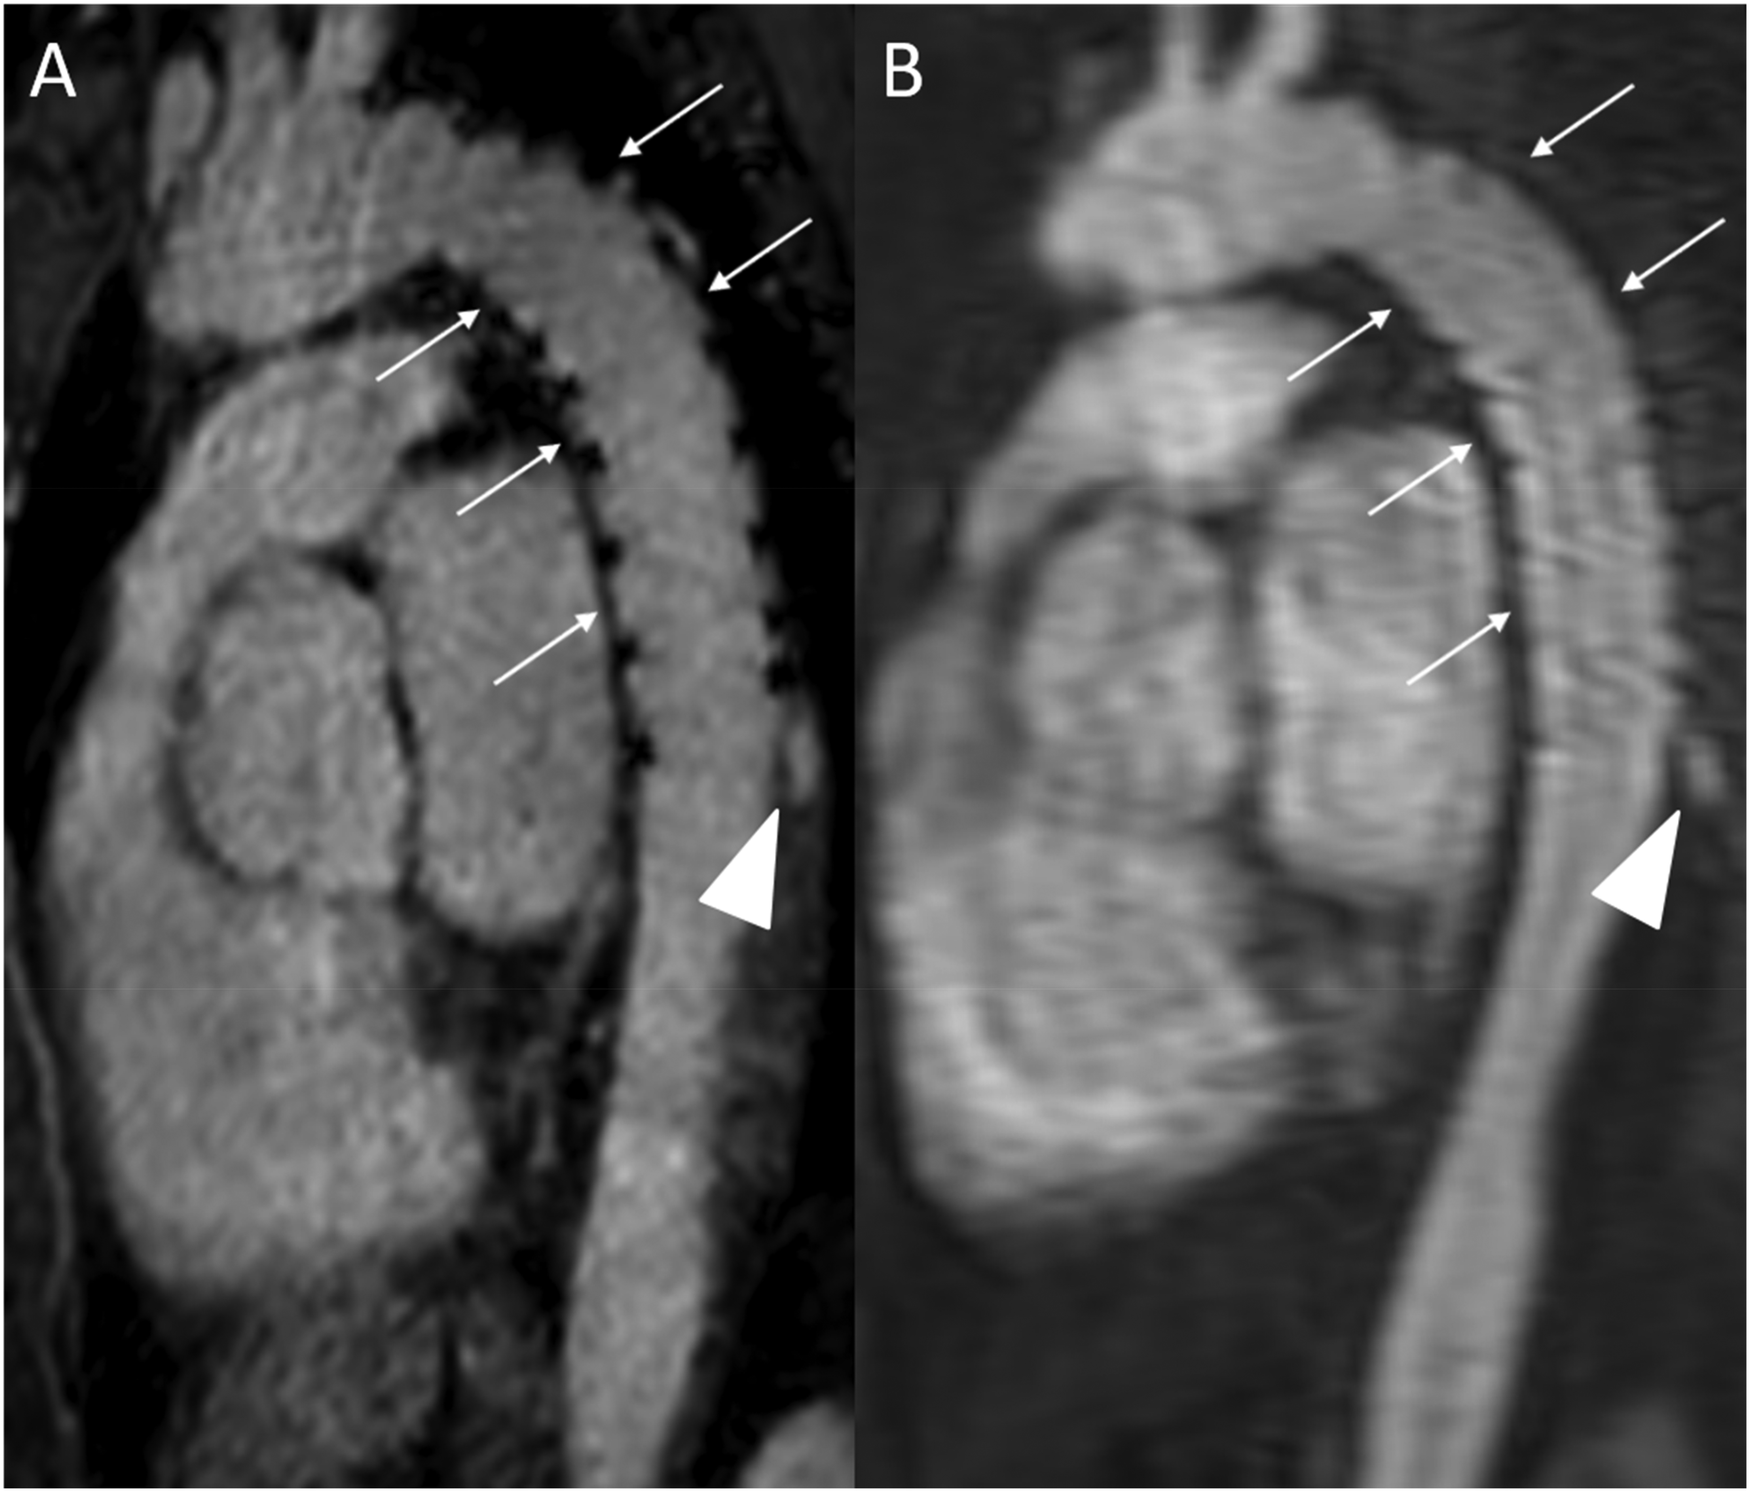

Figure 8

REACT [(A), source image, water-only, parasagittal plane] and CE-MRA [(B), parasagittal plane] in a 46-year-old female patient following supracoronary replacement of the ascending aorta and additional stent graft of the descending aorta due to Stanford type A aortic dissection involving the aortic arch and descending aorta. Note the stronger delineation of stent strats in REACT compared to CE-MRA (thin arrows). Both REACT and CE-MRA present residual inflow (arrowheads) of the false lumen. CE-MRA, contrast-enhanced magnetic resonance angiography; REACT, relaxation-enhanced angiography without contrast and triggering.